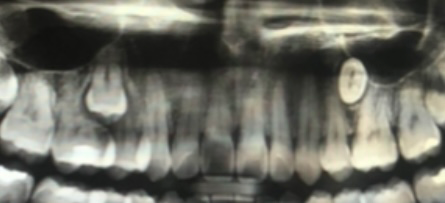

어릴때 작은어금니가 안나서 그냥 없는가보다 하고 지냈는데 치과에 가서 사진을 찍으니 저렇게 숨어있더라고요ㅠㅠㅠㅠ 왼쪽은 옆치아 뿌리도 많이 상한거같은데??

3개 다 뽑아야하는 상황인가요?? 아프지는 않아요

일단은 크게 불편하거나 문제가 없다면 저상태로 그냥 지내셔도 될것같습니다 추후에 문제가 생기면 그때는 매복치랑 같이 뽑으셔야될것같습니다 왼쪽은 큰문제는 없지만 오른쪽은 추후에 문제가 생기면 같이 발치를 하시면될것같습니다.

1. 매복치아의 경우 대학병원급에서 발치가 필요합니다

2. 치열에서 빈공간이 생기는 것은 아니므로 임플란트가 필요하진 않습니다

3. 오른쪽 정상치아(사진상 왼쪽)의 경우 좀 더 검사를 해보고 추가적으로 처치를 해야합니다

매복된 치아로 인해서 불편감이 있다면 해당 치아를 뽑고 교정이나 그 외 치료를 계획을 해야지만 불편감이 없다면 그냥 사용을 해도 크게 문제가 되지는 않습니다.

하지만 치과에서 주기적으로 검진을 받는 것이 좋습니다.

오른쪽 위에 있는 매복치로 인하여 말씀하신 2개의 치아는 발치해야할 가능성이 큽니다. 다만 왼쪽에 있는 매복치아는 다른 치아와 영향이 있는지에 대해서 dental-ct 등의 촬영이 필요해보입니다. 현재 사진은 3차원을 2차원으로 옮긴 것이므로 왜곡이 존재합니다. 따라서 정확한 판단을 위해서는 ct 촬영이 필요합니다.